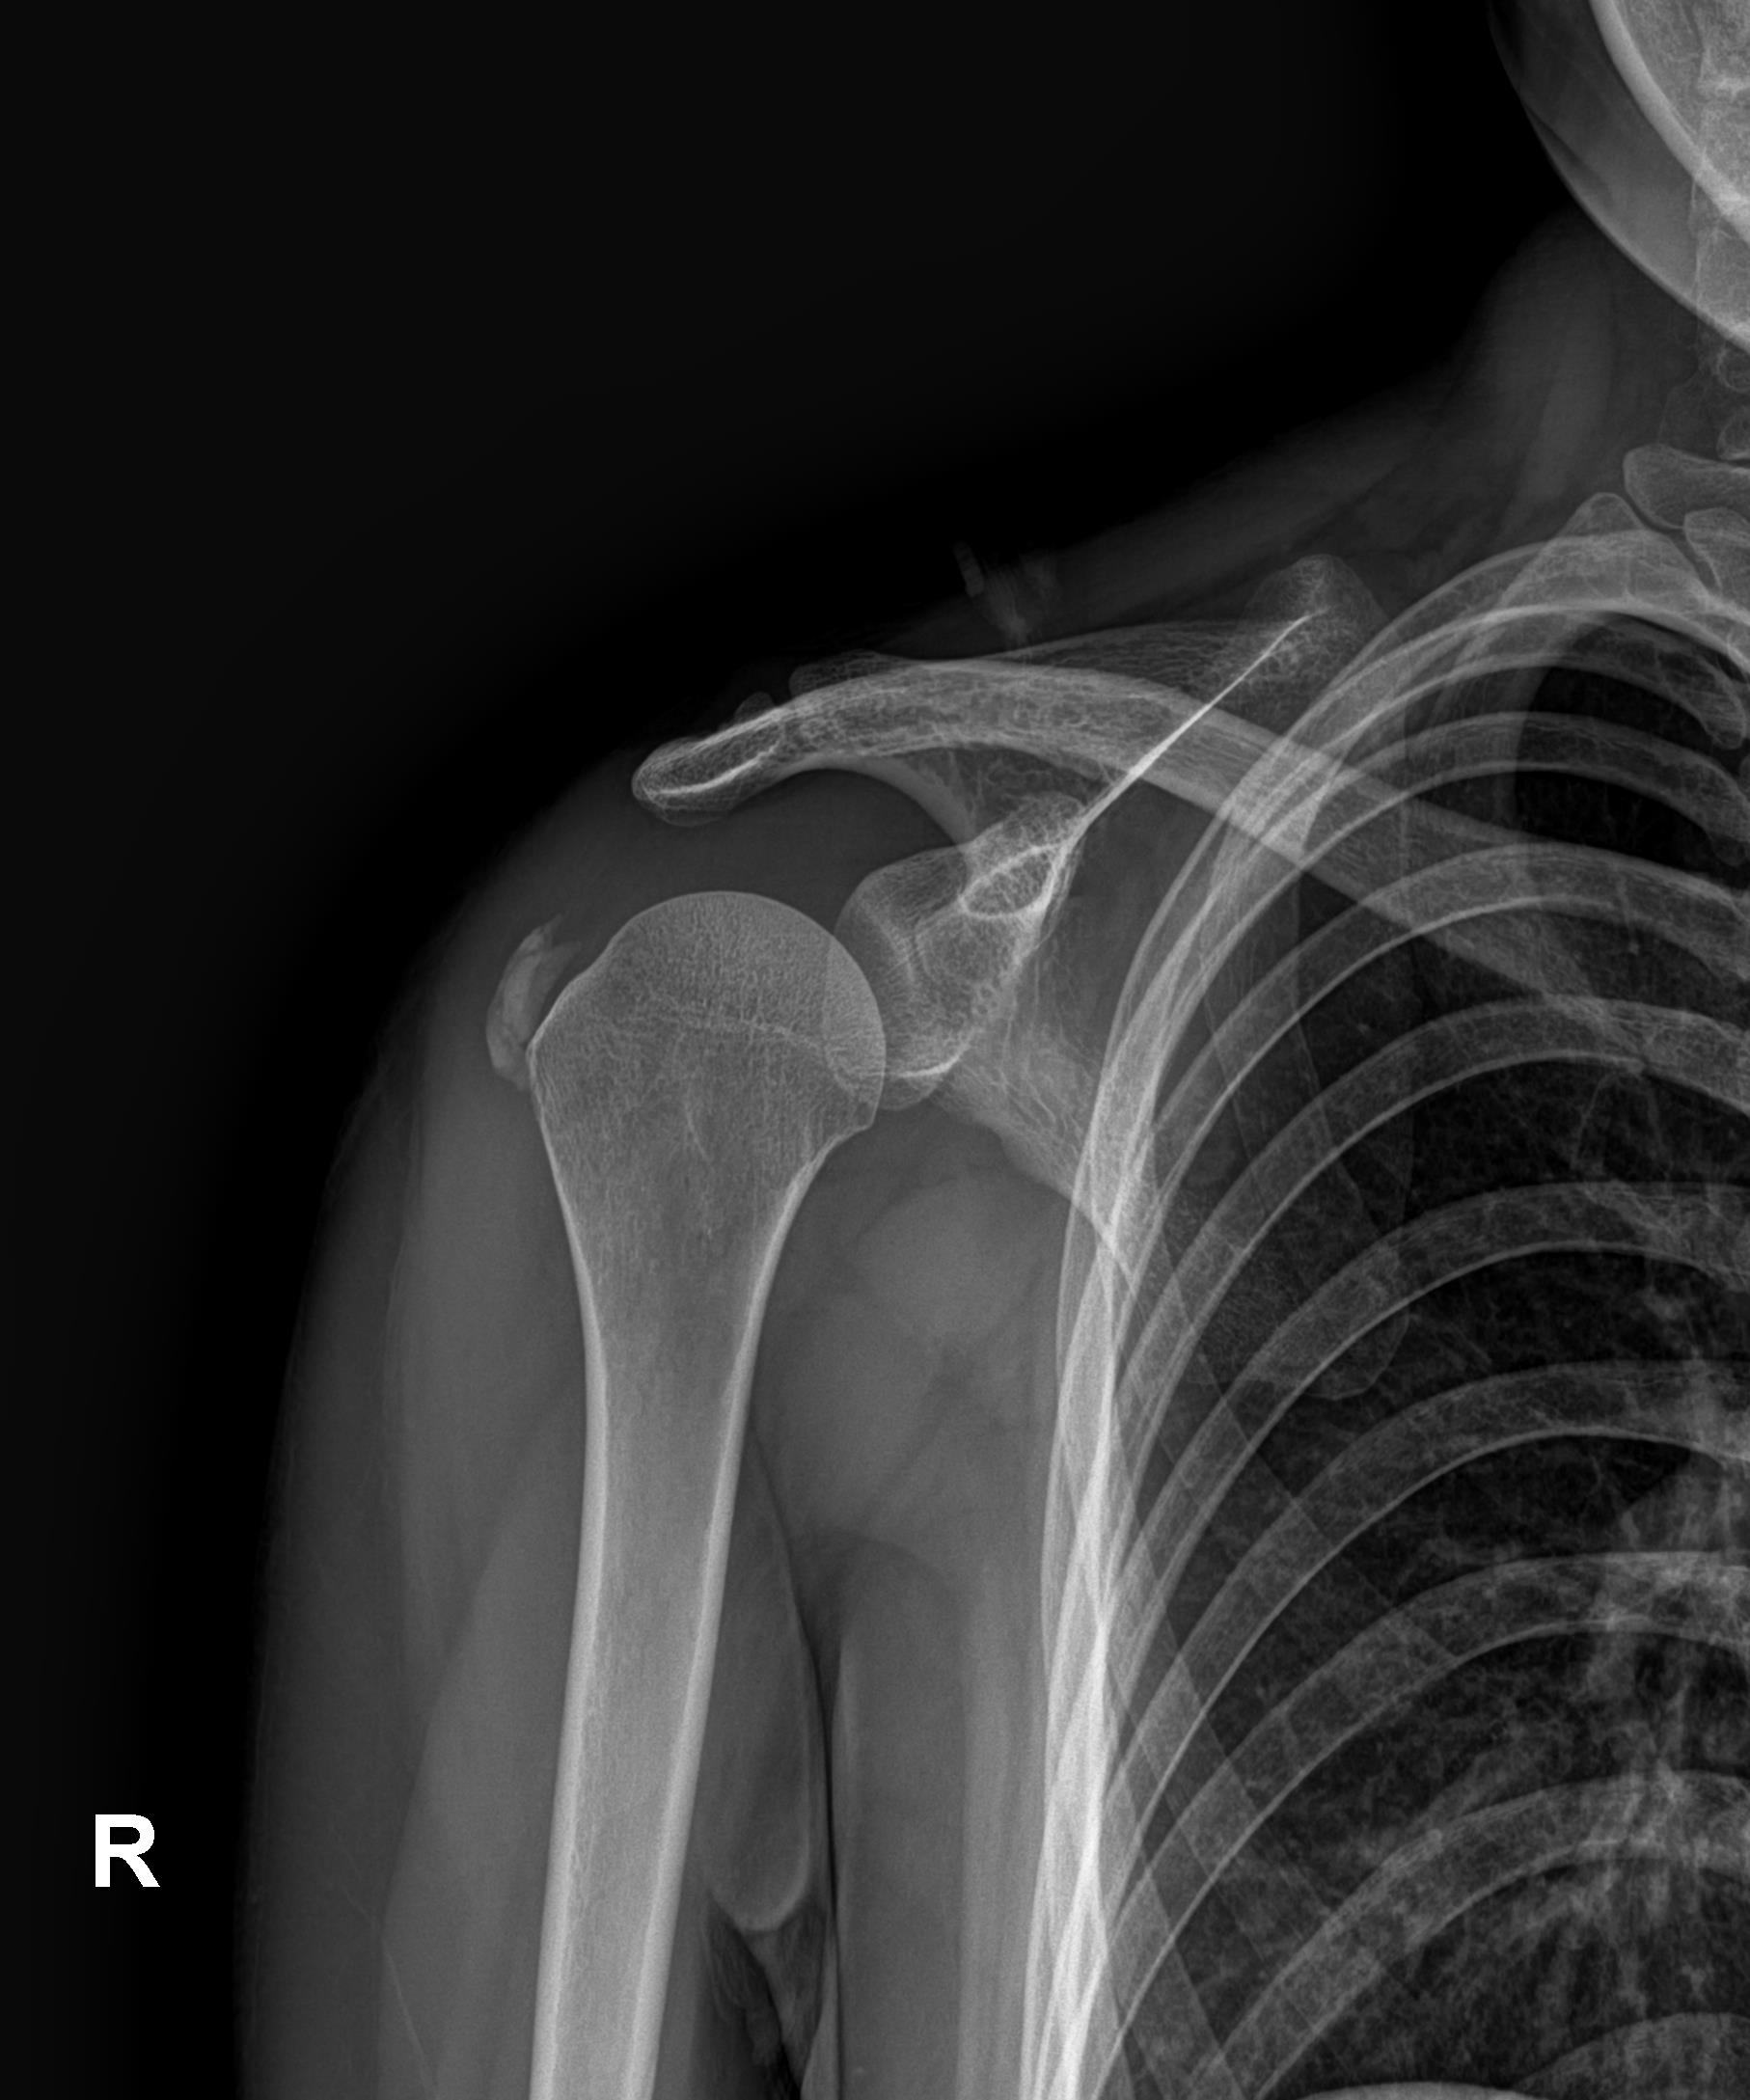

케이스 3: 흡수기 대형 석회 (1회 제거)

환자: 30대 여성, 임신 5개월, 양측 어깨 통증

특이사항:

임신 중이라 X-ray, 전신마취 불가

참을 수 없는 통증으로 시술 결정

시술:

국소마취 하 분쇄흡입술

1.6cm 흡수기 석회 1회 제거

타 병원 실패 후 내원 케이스